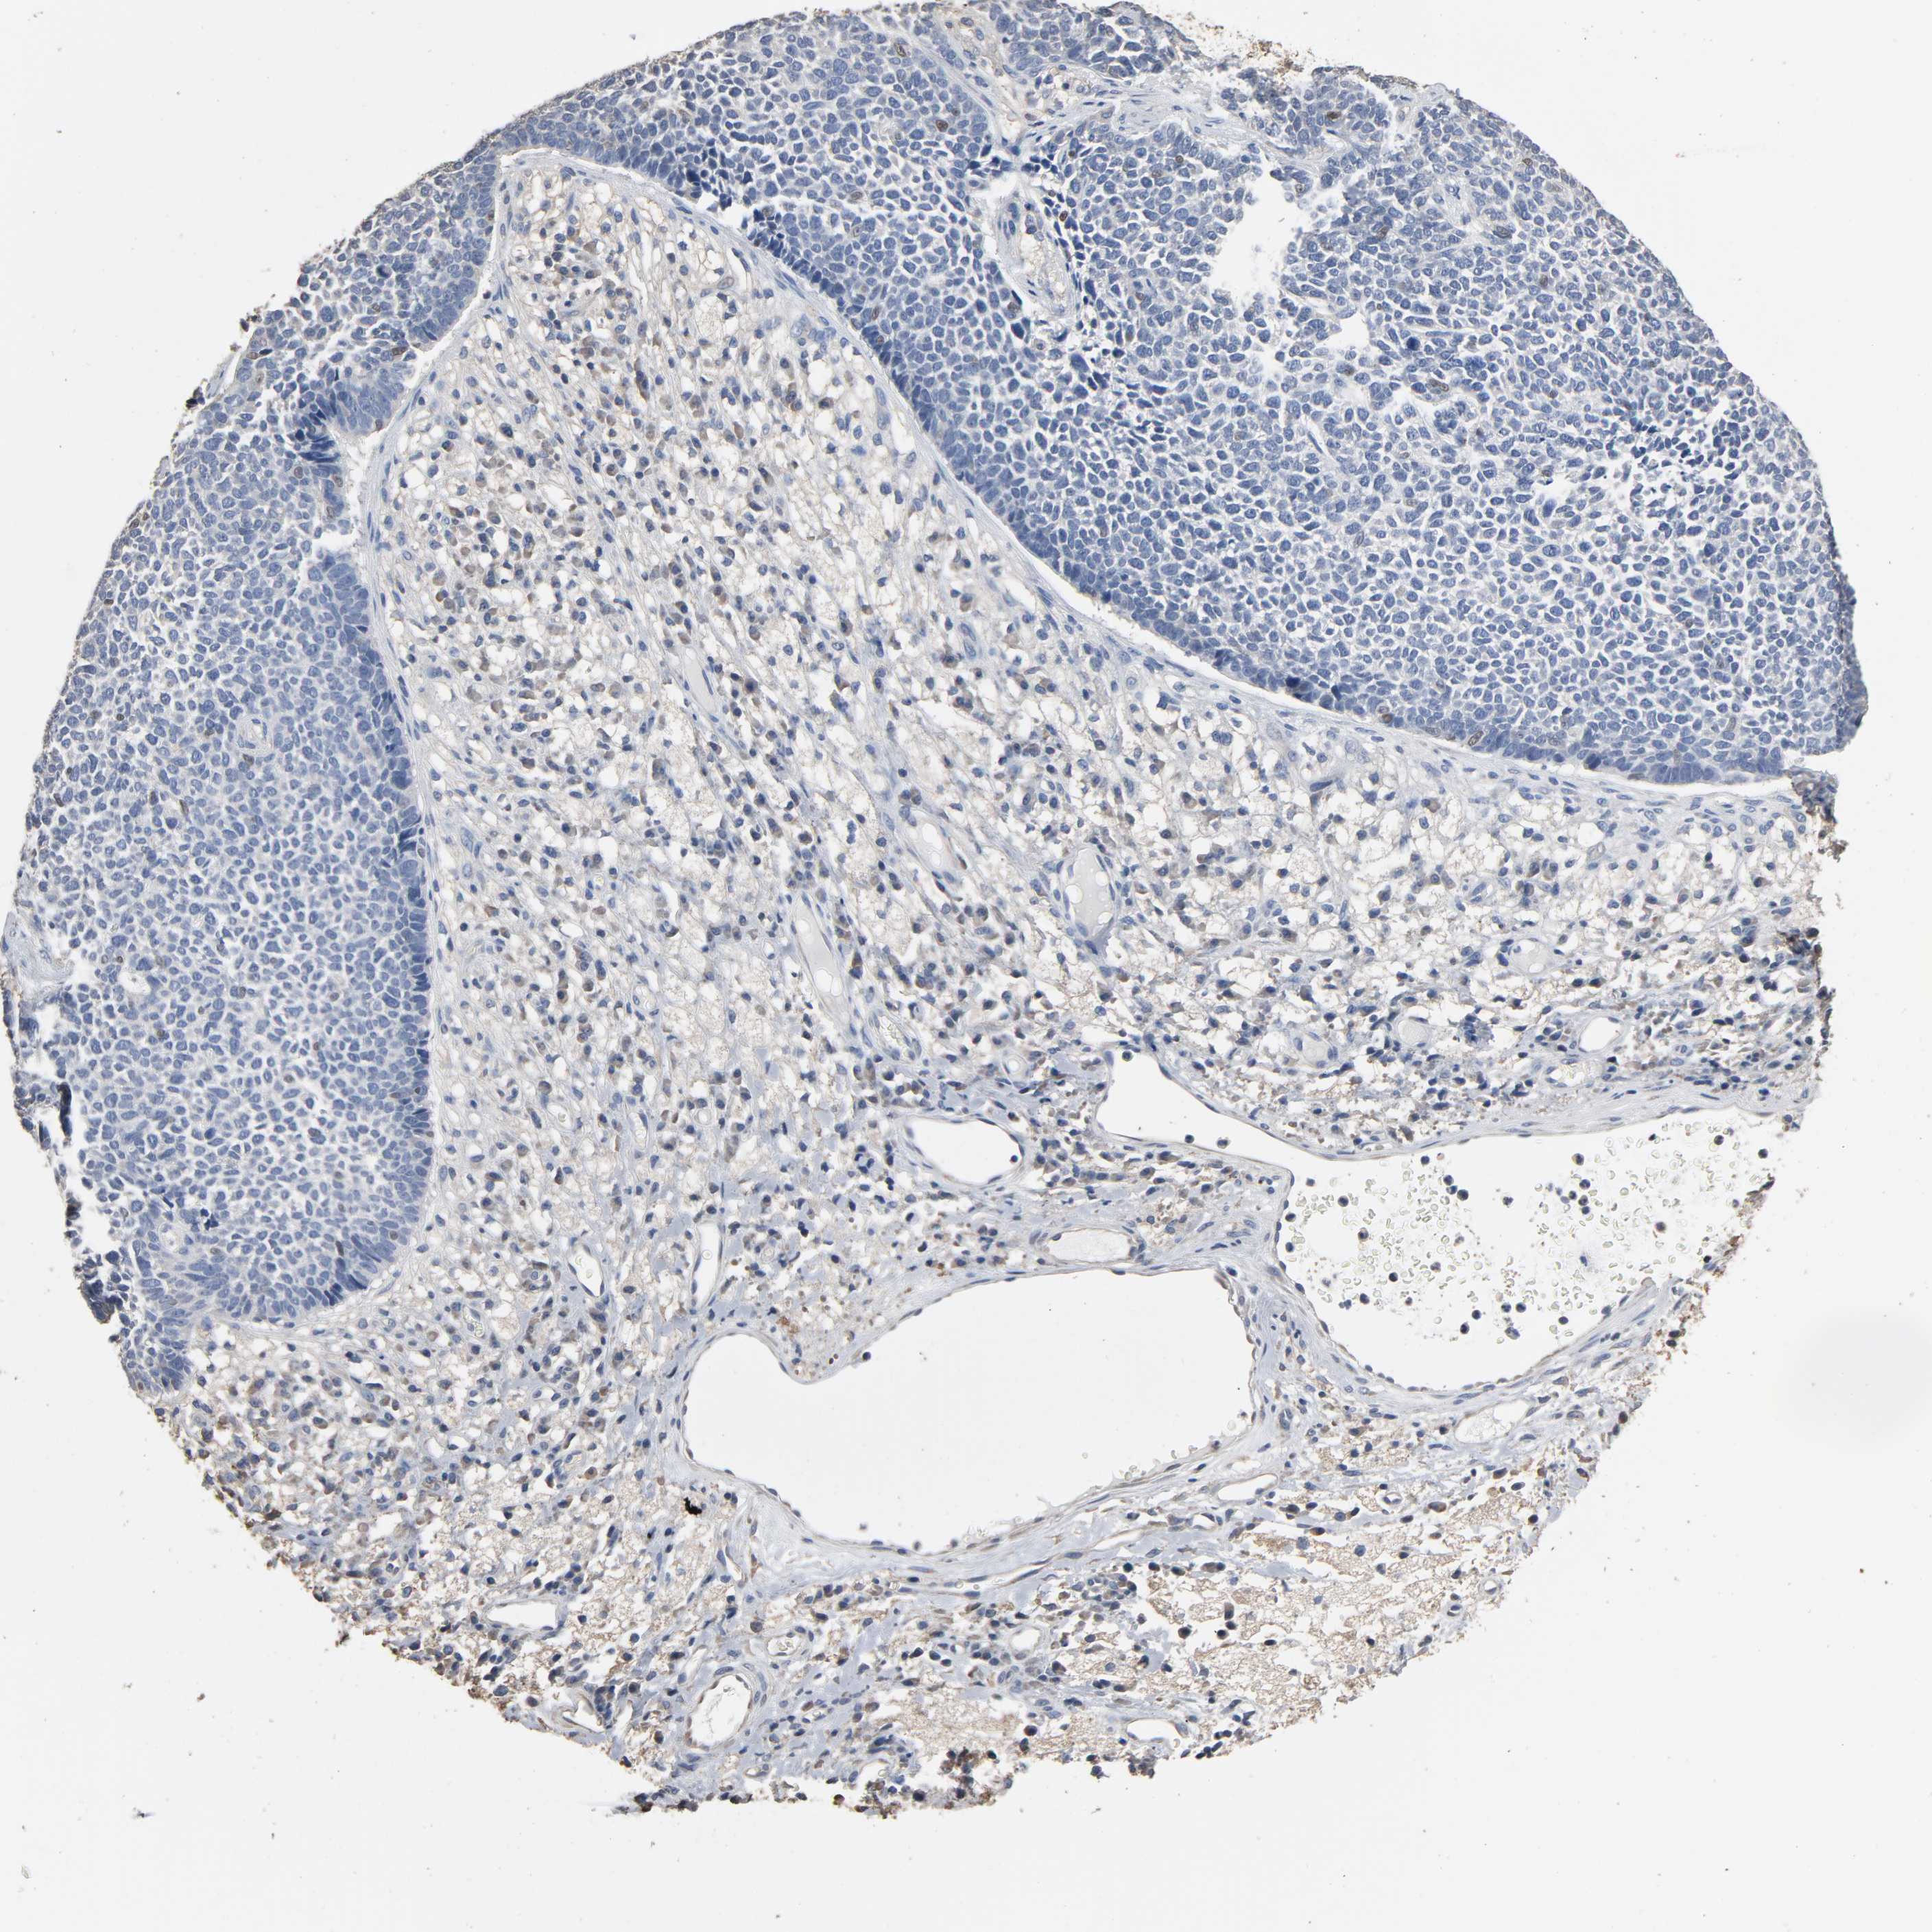

SKIN CANCER - Protein expressioni

A mouse-over function shows sample information and annotation data. Click on an image to view it in a full screen mode. Samples can be filtered based on level of antibody staining by selecting one or several of the following categories: high, medium, low and not detected. The assay and annotation is described here.

Antibody stainingi

Antibody staining in the annotated cell types in the current human tissue is reported as not detected, low, medium, or high, based on conventional immunohistochemistry profiling in selected tissues. This score is based on the combination of the staining intensity and fraction of stained cells.

Each image is clickable and will lead to virtual microscopy that enables deeper exploration of all samples and also displays staining intensity scores, fraction scores and subcellular localization as well as patient and tissue information for each sample.

Antibody HPA001923

Squamous cell carcinoma, NOS

Basal cell carcinoma